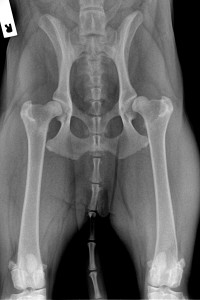

Hip dysplasia – PennHIP

Hip Dysplasia – Juvenile Pubic Symphysiodesis